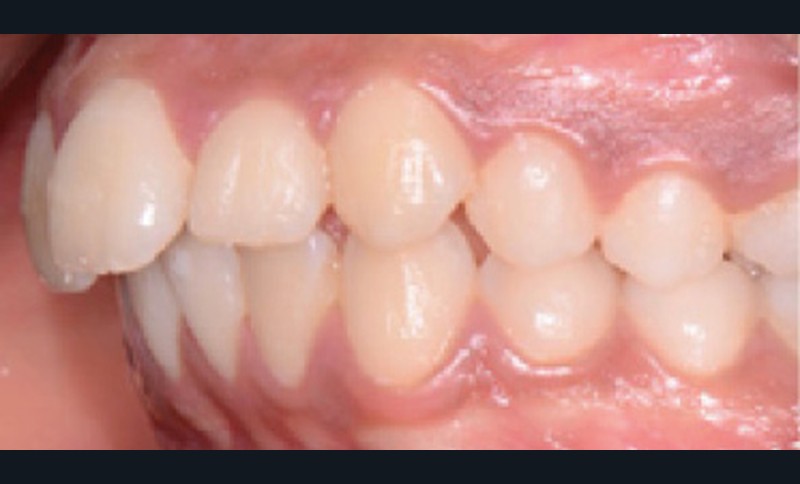

Examen clinique (fig. 1 à 7)

Sur le plan dentaire, elle présente une classe II d’Angle complète, une supraclusion de 4 mm et un surplomb de 6 mm ne correspondant pas au décalage de classe II molaire.